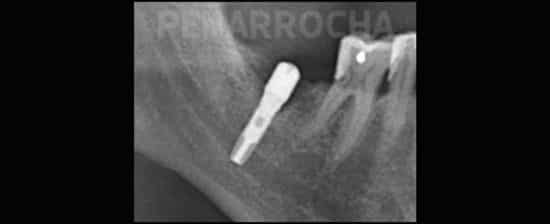

Una de las posibles razones podría ser una periimplantitis periapical, un trastorno infeccioso-inflamatorio que afecta al extremo del implante dental y que puede desarrollarse durante el proceso de osteointegración. No obstante, no hay motivo de alarma: este problema suele tratarse eficazmente mediante una limpieza quirúrgica del área afectada y, en la mayoría de los casos, presenta un buen pronóstico.

Los síntomas y plazos que comentas son característicos de una patología relacionada con los implantes que se conoce como «patología periapical al implante» o «peri-implantitis temprana». Suele ocurrir en aproximadamente el 0,5% de los implantes, y es más frecuente cuando el implante sustituye a un diente que fue tratado con endodoncia o cuando alguno de los dientes vecinos tienen una endodoncia.

También sirve para que, si volviera a pasarte, no asumas como normal el dolor de esos primeros días, y acudas a la clínica dental. La «patología periapical al implante» tiene solución si se trata correctamente y de forma precoz; en un 80-90% de los casos conseguimos salvar los implantes con una sencilla intervención. Y la forma de detectarla es precisamente el dolor agudo durante las primeras semanas: los implantes dentales no duelen, más allá de una ligera molestia postoperatoria que dura unos días y se puede sobrellevar perfectamente con ibuprofeno o paracetamol. Si duelen mucho, es que algo va mal y hay que acudir a la clínica dental a descartar problemas.

Existe una complicación relativamente infrecuente de los implantes dentales que cursa con dolor moderado-severo tras varias semanas de la cirugía de implantes. Se llama periimplantitis temprana, periimplantitis apical o patologia periapical al implante. En el 90% de los casos tiene solución con un sencillo tratamiento quirúrgico, y si no se trata suele desembocar en el fracaso del implante afectado. La clave es diagnosticar si la causa de tu dolor puede ser este problema, para poder solucionarlo.